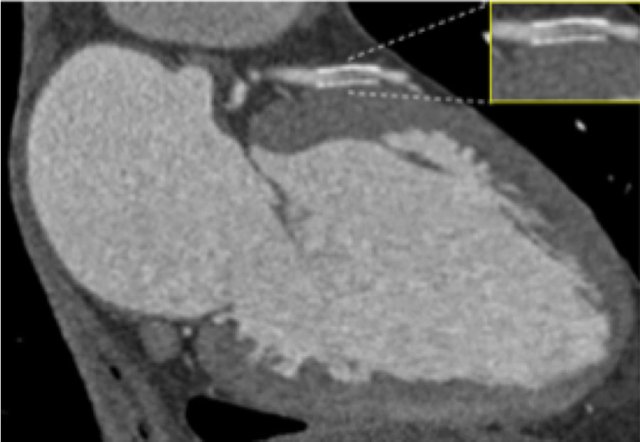

Continue with the next images of the same patient...

Same patient.

Double-oblique (A) and volume-rendered (B) images of the LAD showing the

location and the length of the plaque.

Also, the stenosis in the D2 branch of the LAD can be appreciated on the volume

rendered reconstruction.

Due to the degree of stenosis and the presence of napkin-ring sign (visible on

axial images) this patient underwent ICA where the presence of severe stenosis

was confirmed.